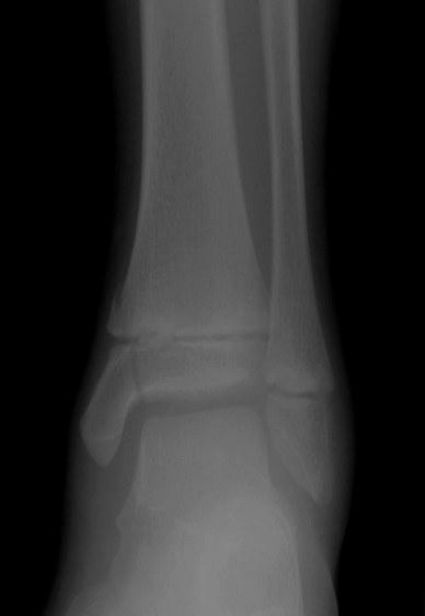

• 2. Match the fracture type to the X-ray.

(a) Greenstick

(b) Salter Harris III

(c) Buckle

(d) Salter Harris IV

X-ray 1: Buckle fracture distal radius and ulna.

X-ray 2: Salter Harris III.

X-ray 3: Salter Harris IV.

X-ray 4: Greenstick fractures.